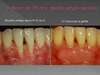

Greffe sur incisives inférieures

Avant (1er photo),

puis à 15 jours de l'intervention (2e photo)